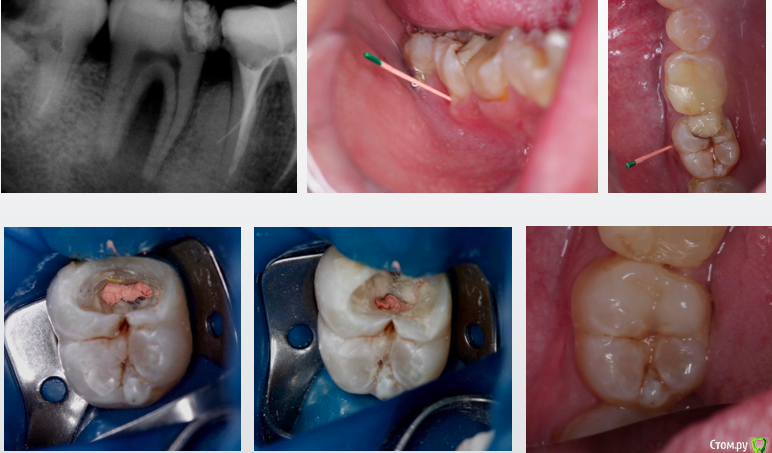

Гарриевич Опубликовано 22 декабря, 2017 Поделиться Опубликовано 22 декабря, 2017 (изменено) админы, если уже создавал такую тему, объедините пожалуйста абсолютно бессимптомный зуб, пациента ничего не беспокоило кроме... да нет, вообще ничего не беспокоило. Лечение в два посещения через гидроксид кальция. Обтурация инжектором. Будут вопросы спрашивайте, каких то еще особенностей сразу не вспомню PS сроки наблюдения 10 месяцев и два года Изменено 22 декабря, 2017 пользователем Гарриевич 8 Ссылка на комментарий

dentikl Опубликовано 23 декабря, 2017 Поделиться Опубликовано 23 декабря, 2017 (изменено) вопрос-1)на фото гутта в проекции фуркации 7 а на рентгене от 26 11.16-в проекции 6. 2)сколько держите под кальием 3)какой кальий используете. спасибо Изменено 23 декабря, 2017 пользователем dentikl Ссылка на комментарий

Гарриевич Опубликовано 23 декабря, 2017 Автор Поделиться Опубликовано 23 декабря, 2017 Скорее всего гутту съехала пока снимки делали. Вложения гидроокиси на 2 недели. В данном случае порошок чистого гидроксида кальция замешанный с водой непосредственно перед внесением. Также испольщую кальцетин технодентовский Ссылка на комментарий